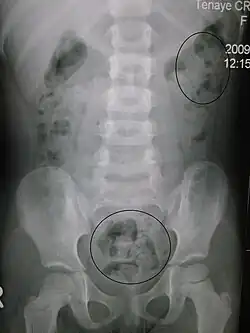

La stitichezza (anche chiamata stipsi o costipazione) è un disturbo della defecazione consistente nella difficoltà, obiettivamente osservabile o soggettivamente percepita, a svuotare in tutto o in parte l'intestino, espellendone le feci.

In media è anche caratterizzata dalla durezza e dalla secchezza delle feci, cosa che ne rende difficile l'espulsione. Questa condizione delle feci può essere dovuta a un eccessivo assorbimento di acqua da parte del colon e spesso, specie nella stipsi cronica, è legata a episodiche o ricorrenti coprostasi ma non ne è obbligatoriamente connessa. Il soggetto può infatti avvertire difficoltà ad evacuare a prescindere dalla lentezza del traffico fecale, tratto che invece caratterizza sempre la coprostasi.

La stipsi è il risultato di un'alterazione nella propulsione del bolo fecale e/o della evacuazione dello stesso. I disturbi della progressione possono essere correlati ad una ridotta massa fecale (diete incongrue, scarso introito di fibre, alterazioni elettrolitiche), ad affezioni organiche del colon che meccanicamente impediscono il passaggio del bolo fecale, oppure ad alterazioni funzionali intestinali, quali la stipsi cronica a lento transito o l'atonia coli. I disturbi della evacuazione sono anche correlabili ad alterazioni organiche della regione ano-rettale (ragadi, fistole, emorroidi, neoplasie ano-rettali, morbo di Hirschsprung, tubercolosi intestinale) o ad alterazioni funzionali, quali la dischezia rettale o la sindrome del perineo discendente.

Le dosi fecali sono scarse e spesso hanno un aspetto molto secco e duro; la defecazione non è mai completa. Come esame complementare si può usare la manometria colica delle 24 ore e clisma opaco ed eventualmente la defecografia. Può essere utile per monitorizzare nel tempo la consistenza delle feci e i miglioramenti ottenuti con la terapia l'uso della Bristol stool scale.[12]